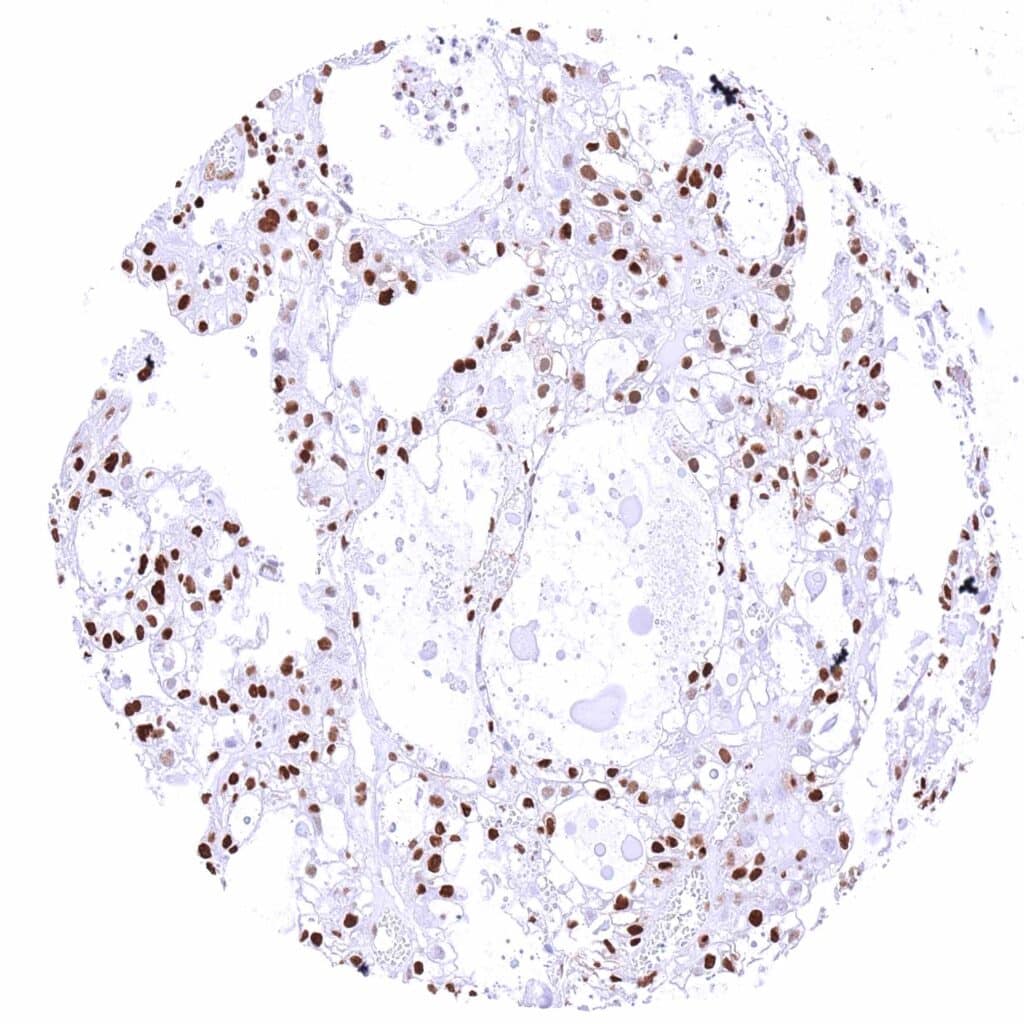

Lung – Adenocarcinoma with strong, predominantly nuclear p27 staining of most tumor cells.